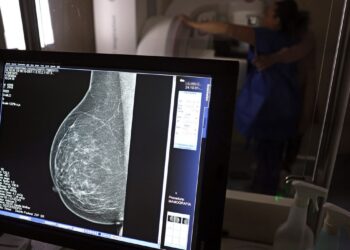

AGU processa médico que apontou mamografia como causadora de câncer

O Ministério da Saúde decidiu recomendar a mamografia para mulheres de 40 anos ou mais, já que é a faixa ...

Buscando conscientizar sobre a importância de realizar os cuidados com a mama, 5 de fevereiro no Brasil é o Dia ...